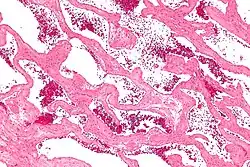

Micrograph of a cavernous liver hemangioma. H&E stain.

Liver cavernous hemangioma

Cavernous hemangiomas are erroneously called the most common benign tumors of the liver.[14] Usually one malformation exists, but multiple lesions can occur in the left or right lobe of the liver in 40% of patients.[3] Their sizes can range from a few millimeters to 20 centimetres. Those over 5 cm are often referred to as giant hemangiomas.[3] These lesions are better classified as venous malformations.